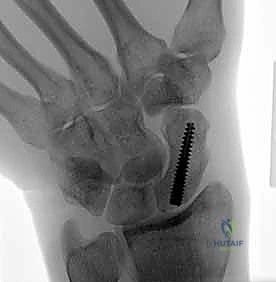

تقنية "التثبيت عن طريق الجلد" (Percutaneous Fixation) هي إجراء جراحي طفيف التوغل (Minimally Invasive). بدلاً من فتح الرسغ، يقوم الجراح بإجراء ثقب صغير جداً في الجلد (لا يتجاوز 3-5 مليمترات). من خلال هذا الثقب، وباستخدام جهاز الأشعة السينية المباشر في غرفة العمليات (C-arm Fluoroscopy)، يتم إدخال سلك توجيهي دقيق، ثم يتم إدخال مسمار خاص يسمى "مسمار ضغط بدون رأس" (Headless Compression Screw) مثل مسمار هيربرت (Herbert Screw).

هذا المسمار العبقري يتم دفنه بالكامل داخل العظم (تحت سطح الغضروف حتى لا يحتك بالمفاصل الأخرى)، ويتميز بوجود أسنان لولبية (Threads) في طرفيه بمسافات مختلفة. هذا التصميم يجعله يسحب طرفي الكسر ويضغطهما معاً بقوة هائلة (Compression)، مما يحفز التئام العظم بسرعة فائقة ويمنع أي حركة بين طرفي الكسر.